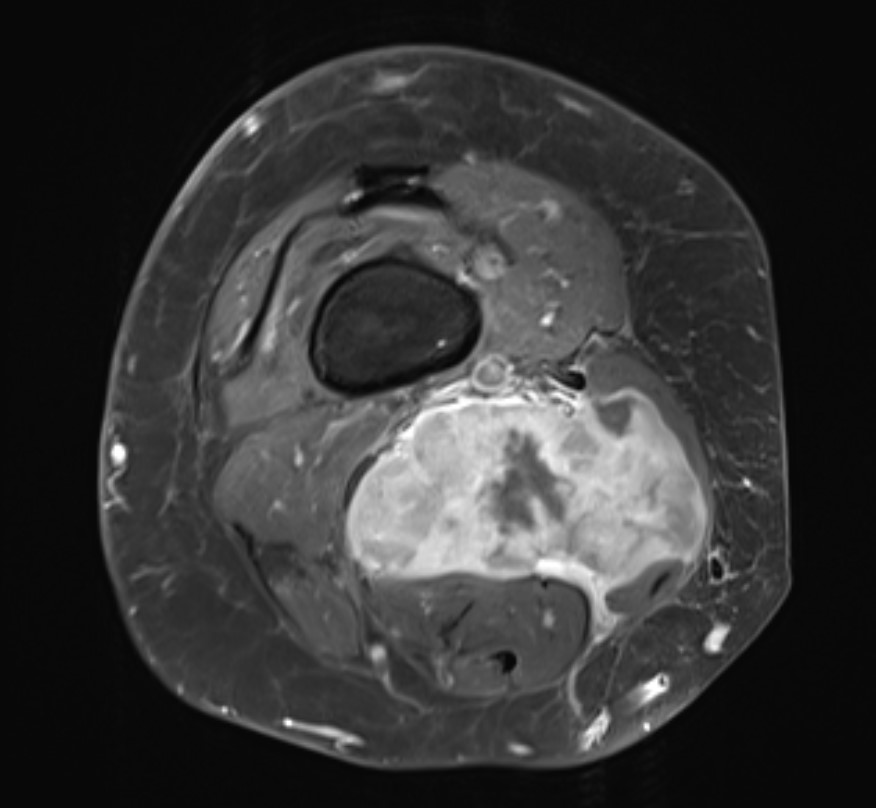

MRI

Sarcoma knee